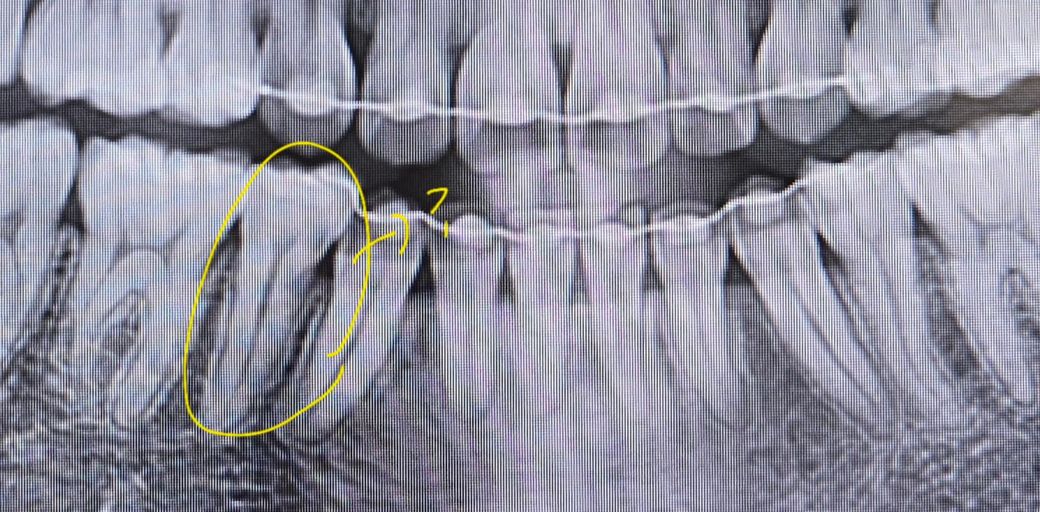

사랑니 전문 병원에서 2년전 사랑니를 빼기 전에 찍은 사진 (1) 과 2년 후에 사랑니를 빼고 나서의 사진 (2) 사이에 교정기를 단 쪽에 뭔가 파여 있는 듯 한 자국이 보이더군요... 그래서 1개월 뒤 타 치과에서 검진(3)을 받아봤는데 충치는 없다고 진단해주셨습니다... 원래도 시림 증상도 없고 멀쩡해서 안심이긴 하지만 타 선생님이 보시기에도 충치가 아닌지 궁금합니다 ㅜ 점점 신경 쪽하고 가까워지고 있는 것 같기도 해서요...🥺

파노라마 엑스레이는 다양한 왜곡, 음영이 있어서 판단이 어렵고요 충치 의심 부위에 치근단 엑스레이를 찍어봐야합니다

사진으로 보이는 부위는 방사선사진이 어둡게 보이는 곳입니다. 인접면의 충치를 정확하게 판단하기 위해서는 치근단사진이나 육안검사가 필요할 것으로 생각됩니다.

방사선 사진에는 치경부 소환 이라는 것이 있는데요 말씀하신 치아의 목 부위(머리와 뿌리 사이)가 다른 곳 보다 더 까맣게 보이는 것입니다. 일종의 착시현상같이 저렇게 보이는 것인데 사진을 찍을때마다 심하기도, 정상으로 보이기도 합니다. 육안으로 봤을때 괜찮고 증상이 없으시다면 크게 걱정하지는 않으셔도 되겠습니다.

사진상으로는 충치가 깊어 보이거나 그렇진 않습니다. 지금처럼 관리를 잘하시면될것같습니다.

사진의 선명도에 따라 달라보일 수 있지만 가능성이 보입니다. 치과에서 해당 치아 문의해보시면 좋겠습니다.